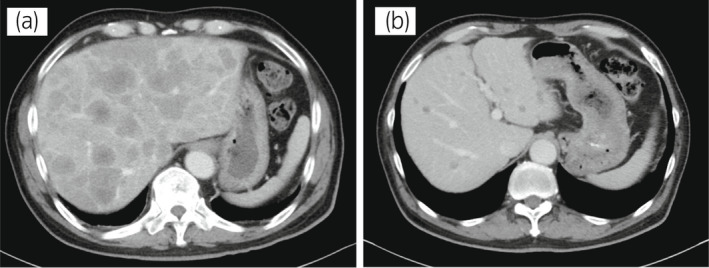

70 歲男性被診斷為轉(zhuǎn)移性 PC,cT3bN1M1b,Gleason 評(píng)分(GS)為 4 + 5 = 9,前列腺特異性抗原(PSA)水平為 40.8ng/ml,3 年前伴有胸椎轉(zhuǎn)移。 對(duì)前列腺進(jìn)行聯(lián)合雄激素阻斷 (CAB) 治療和質(zhì)子放射治療 (78.0Gy/39fr)。 PSA 水平降至 <0.01ng/ml,CAB 在 2.5 年后停止。 停止 CAB 五個(gè)月后,他出現(xiàn)背痛,PSA <0.01 ng/ml。 計(jì)算機(jī)斷層掃描 (CT) 掃描檢測(cè)到多處肝、骨和淋巴結(jié)轉(zhuǎn)移,神經(jīng)元特異性烯醇化酶 (NSE) 水平高達(dá) 171ng/ml(圖 1a)。 骨轉(zhuǎn)移活檢顯示神經(jīng)內(nèi)分泌前列腺癌 (NEPC) 的診斷(圖 2),患者被轉(zhuǎn)診至佳學(xué)基因合作醫(yī)院。 內(nèi)分泌腫瘤正確治療醫(yī)生用順鉑、依托泊苷和亮丙瑞林治療。 第三個(gè)療程后,轉(zhuǎn)移部位明顯縮?。▓D 1b)。 順鉑和依托泊苷治療 1 年,但患者因神經(jīng)病變要求停藥。 他開(kāi)始服用恩雜魯胺。 治療 3 個(gè)月后,患者出現(xiàn)背痛和左鎖骨下淋巴結(jié)腫大(圖 3a)。 肝轉(zhuǎn)移保持不變,順鉑治療后縮小。 通過(guò)腫瘤正確用藥850基因檢測(cè)證實(shí)了 BRCA2 突變。根據(jù)基因檢測(cè)結(jié)果,主治腫瘤科醫(yī)生給予了奧拉帕尼。 三個(gè)月后,背痛好轉(zhuǎn),淋巴結(jié)轉(zhuǎn)移縮小,確定為部分緩解(PR)(圖3b)。 肝轉(zhuǎn)移灶保持不變。